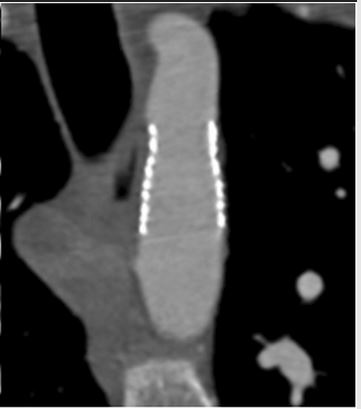

Fig 3d Boccalini et al Jan 2019The aim of this study was to evaluate the post-implantation computed tomography (CT) image quality of different types of stents that are used to treat aortic coarctation. By subjectively scoring CT scans for image quality and measuring the amount of stent-induced blooming artefacts, the authors were able to conclude there is a substantial variation in CT image quality and blooming artefacts for different stent types used to treat aortic coarctation.

Article: Computed tomography image quality of aortic stents in patients with aortic coarctation: a multicentre evaluation